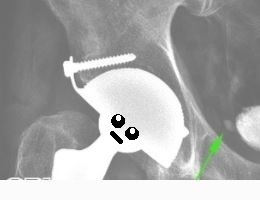

А так он выглядит на рентгенограммах (на эндопротезы с обеих сторон в данном случае можно не обращать внимания, пост не о них).

Мужчина, 69 лет. Мочевой пузырь обычной формы, с неровными, достаточно четкими контурами (может быть признаком избыточно развитой слизистой оболочки). По правой стенке мочевого пузыря определяется стойкое депо контраста (это значит на нескольких снимках с промежутком в 7 минут), размером 8,5х5 мм (вероятно, дивертикул).